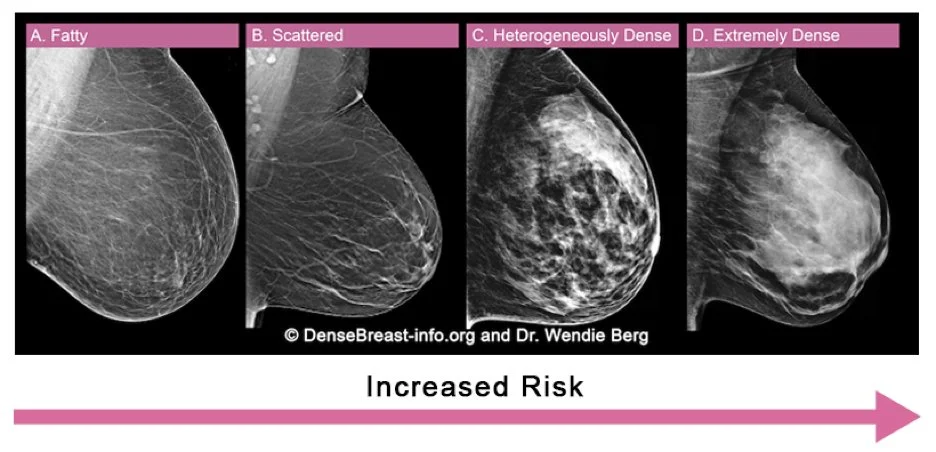

For many women, the screening mammograms note “dense breast tissue.” For them, the recommendation is a screening breast ultrasound. Dense breast tissue increases your risk of a breast cancer —and makes it hard for a radiologist to spot one by mammogram alone. Ultrasound can often find such abnormalities. Financial note: Frustratingly, insurance coverage of screening ultrasounds hasn’t been uniform by state or by insurer. I’m glad to share that an 2026 update to the Affordable Care Act requires that this imaging be at no patient cost, just like mammograms.

In every mammogram report, breast tissue is categorized from A to D:

A cancer shows up as white on mammogram, as does dense breast tissue. A picture is worth a thousand words—in this case, demonstrating how much harder it is to see a breast cancer in dense breast tissue!